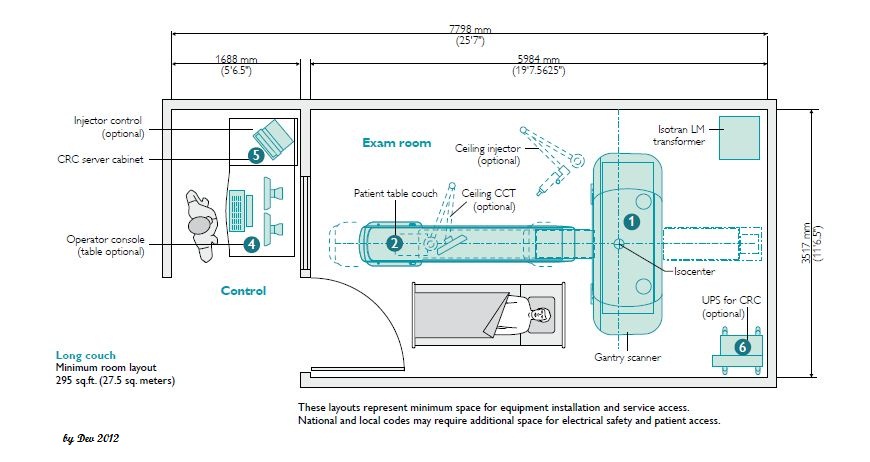

wallpaperaccess.comCt Scan Room Floor Plan - Floorplans.click

wallpaperaccess.comCt Scan Room Floor Plan - Floorplans.click

www.shutterstock.comCt Scan Room Floor Plan - Floorplans.click

www.shutterstock.comCt Scan Room Floor Plan - Floorplans.click

www.vecteezy.comCT Scan Room Size: What Do You Need To Know? - CTMRIHUB

www.vecteezy.comCT Scan Room Size: What Do You Need To Know? - CTMRIHUB